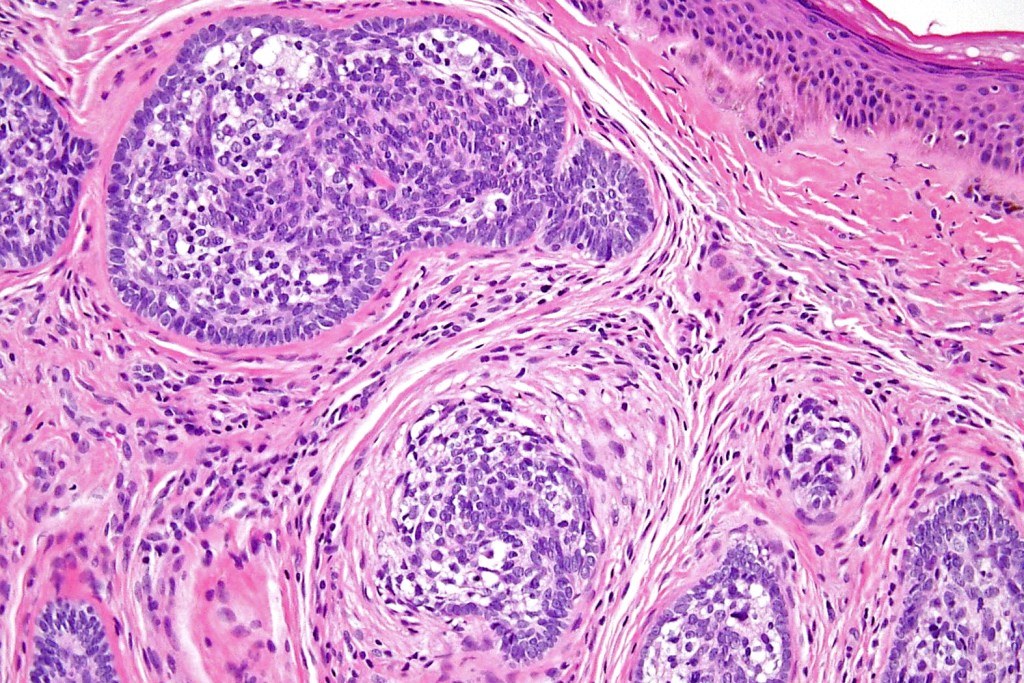

•Dermal nodule, rarely extends into subcutaneous fat

•Irregular lobules of epithelial cells embedded in a dense fibrous stroma

•Peripheral rim of darkly staining basaloid cells surrounding larger pale staining cells with vesicular nuclei with often prominent eosinophilic nucleoli

•Central cells PAS positive (glycogen)

•No pleomorphism or mitotic activity

•No retraction artifact or stromal mucin

•Admixed lymphocytes (an obligatory feature)

•Germinal centers sometimes present